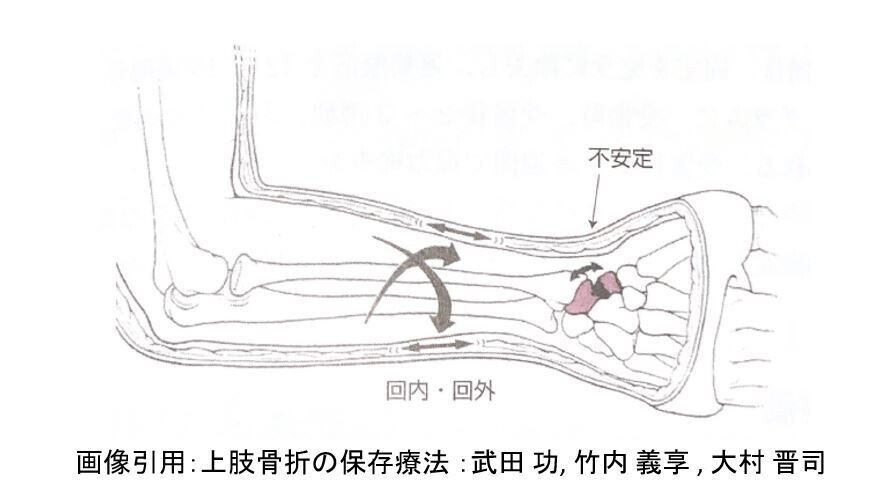

このとき考察されたのが

前腕回内回外時の舟状骨骨折部に与える影響だ

付随するように

また,Russeら, Eddelandraら

どちらもLong thumb spica castを行って

良好な結果を報告している

だがしかし,これに対して

Falkenbergらは

cadaver(ご献体)を使った実験で

前腕回内外運動は舟状骨骨折部の可動性に

影響がなかったことを報告